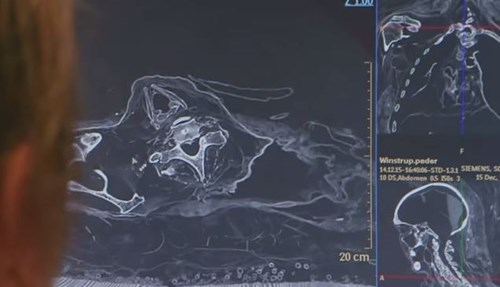

Научници решиле да скенираат мумија на познат бискуп. Не ни помислиле дека ќе ги снајде ОВА!

Никој не би можел да се посомнева дека таков човек, каков што беше бискупот Винструп, би можел да крие таква мрачна тајна.Повеќе од 350 години бискупот Педер Винструп, лежел мирно […]